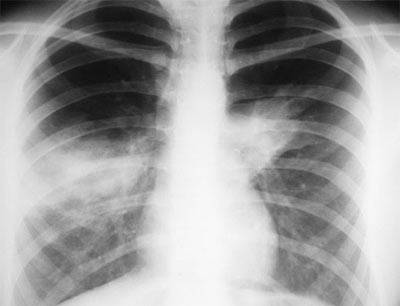

- Сделать рентген (к сожалению, пока не в каждой больнице есть аппаратура для обследования лежачих больных). Скопившаяся в лёгких жидкость на плёнке даст тени и уменьшение прозрачности, но «картинка» будет неотличима от других лёгочных болезней – например, бронхопневмонии.

ТЭЛА чаще развивается у больных, страдающих тромбофлебитом нижних конечностей и таза, пребывающих длительное время в постели, при мерцательной аритмии, в послеоперационном периоде. У молодых женщин лёгочные тромбоэмболии иногда встречаются при использовании пероральных контрацептивов. Для инфаркта лёгкого характерна боль в груди, при полисегментарном поражении — одышка и цианоз, тахикардия и артериальная гипотензия. Аускультация может выявить ослабление дыхания и шум трения плевры. При поражении одного сегмента на рентгенограммах выявляют гомогенную тень треугольной формы, обращенную основанием к висцеральной плевре, а верхушкой — к воротам лёгких. Информативно проведение перфузионного радиоизотопного сканирования, при котором обнаруживают ишемические «холодные» зоны в лёгких. На ЭКГ появляется картина острой или подострой перегрузки правых отделов сердца.

- рентгенография органов грудной клетки;